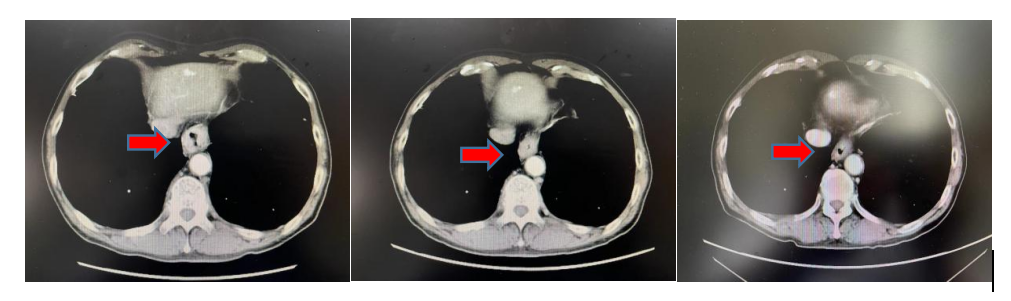

患者男性,70岁,多年慢性阻塞性肺疾病史,饮酒30余年。2022年3月因进食梗阻进行性加重就诊于我院,行胃镜检查示:距门齿38-40cm处可见管腔变窄,环周浸润,并可见约1.0×1.0cm隆起性病变,表面粗糙不平。活检3块,质脆,送检,病理示:(食管下段-贲门)低分化腺癌。行胸部增强CT提示:食管下段管壁增厚,贲门区不均增厚,境界不清,增强后呈明显不均强化,相应管腔变窄,周围脂肪间隙显示不清,符合贲门癌表现。目前诊断为:P食管下段-贲门癌cT3N0M0ⅡA期。

放疗前,放疗中,放疗后增强CT对比图像